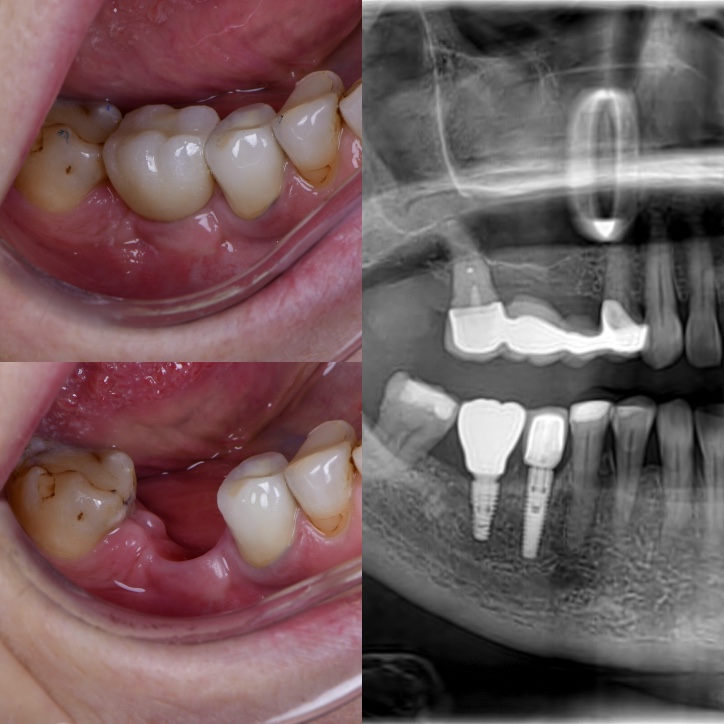

Zubni implantati su najmodernija i najprirodnija zamjena za izgubljeni zub. Nakon što je zub izvađen, implantat će poslužiti kao nadomjestak korijena prirodnog zuba. Ovaj mali „vijak“ ugrađuje se u kost gdje je prije bio prirodni zub.

Implantat se sastoji od tri dijela: kruna, suprastruktura i titanski implantat, koji se nalazi unutar kosti. Zubni implantat zamjenjuje jedan zub bez utjecaja na zdravlje susjednih zuba. Nedostatak je što su skuplje rješenje od zubnog mosta ili mobilne proteze.

Kao i kod trajnosti ostalih fiksnih radova, najveći utjecaj ima pacijentovo pridržavanje uputa o oralnoj higijeni.